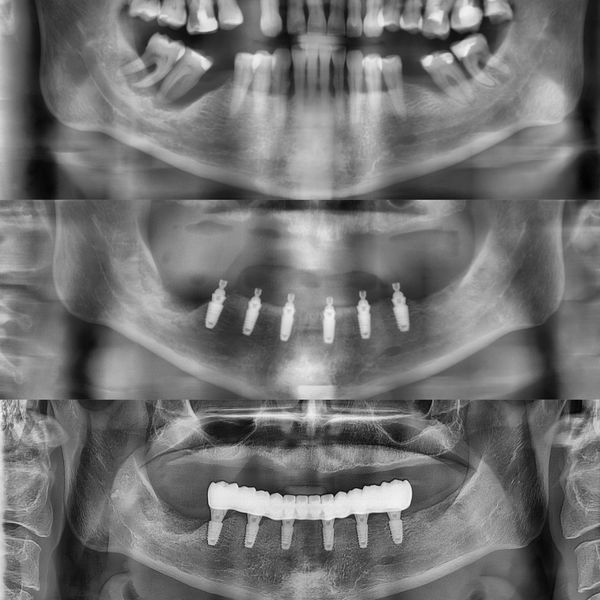

Провели компьютерную томографию челюстей, на которой выявили снижение высоты межзубных перегородок на 2/3 длины и оголение корней всех зубов на 1/2 длины. Также определили, что объём костной ткани достаточный по высоте и ширине для установки имплантатов.

- Установили 6 имплантатов на нижней челюсти с использованием навигационного хирургического шаблона. На период приживления имплантатов изготовили временный акриловый протез с опорой на эти имплантаты. Продолжительность второго этапа — 4 месяца.

- Выполнили постоянное протезирование с использованием мультиюнитов (переходных элементов для фиксации протезов). Изготовили несъёмный цельноциркониевый протез, армированный титановой балкой. Этот материал является самым эстетичным и износостойким.

Имплантаты надёжно закрепились в кости, на контрольном рентгеновском снимке патологических изменений вокруг них не было. Слизистая оболочка в области имплантатов также без патологических изменений, бледно-розовая, безболезненная.